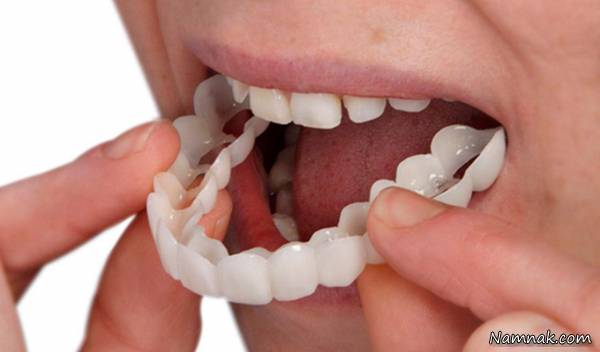

برای جا افتادن دندان مصنوعی چه کنیم؟

برای افرادی که به دلیل بیماری یا آسیب دندانهای خود را از دست دادهاند، دندان مصنوعی میتواند لبخند آنها را بازگرداند و در انجام فعالیتهای روزانه مانند غذا خوردن و صحبت کردن به آنها کمک کند. با این حال، عادت کردن پروتز ممکن است زمان ببرد، و ممکن است فرد هفته ها طول بکشد تا به دندان مصنوعی عادت کند. ممکن است فرد احساس کند که دندان ها در دهان لق هستند تا زمانی که ماهیچه های گونه و زبان یاد بگیرند که آنها را نگه دارند. احساس ناراحتی یا درد خفیف از دندان ها غیرعادی نیست.

یکی از مهم ترین نکات در هنگام قرار دادن و استفاده از دندان مصنوعی، توجه به ویژگی های فردی است. هر کس به طور متفاوتی درمان می کند. بسته به اینکه پروتز کامل یا جزئی دارید، زمان تنظیم می تواند متفاوت باشد. زیرا پروتزها می توانند با گذشت زمان با دهان نامتناسب شوند و شرایط لثه تغییر کند. بنابراین، مصرف هر گونه داروی تجویز شده در دوران انتقال به شما کمک می کند تا از ناراحتی در طول این انتقال جلوگیری کنید. در نهایت، چندین ماه پس از استفاده از دندان مصنوعی به طور منظم به دندانپزشک خود مراجعه کنید. حتی اگر دندان های جدید دارید، چکاپ منظم و حفظ سلامت دهان و دندان در خانه بسیار مهم است. محصولاتی مانند دهانشویه که 99 درصد میکروب ها را از بین می برند لبخند شما را زیبا و طبیعی می کنند. در این لینک بهترین متخصص ارتودنسی در شیراز را به شما معرفی کردیم.

اگر دندان مصنوعی در کلینیک دندانپزشکی پایه و طبق قوانین و با در نظر گرفتن وضعیت فک و لثه ساخته شود، عادت کردن به آن کار سختی نیست. در غیر این صورت بهتر است وقت و هزینه را هدر ندهید و از روش پروتز ثابت استفاده کنید.